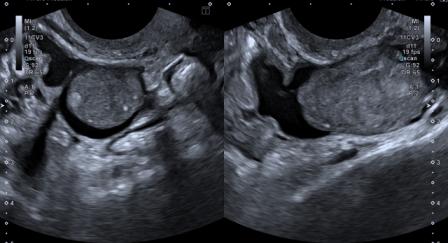

Ultrasound findings were as follows –

Figure 1: Distended endometrial cavity shows a fluid collection with mobile internal echoes.

Figure 2: A lobulated cystic lesion measuring 11 x 3 cm seen in the left adnexa, suggestive of hydrosalpinx. It showed small eccentric solid nodular component along the wall, with presence of mobile internal echoes in the fluid.

Based on clinical presentation and ultrasound findings, a diagnosis of hematometra with left hydrosalpinx / hematosalpinx was made. Follow-up was recommended.